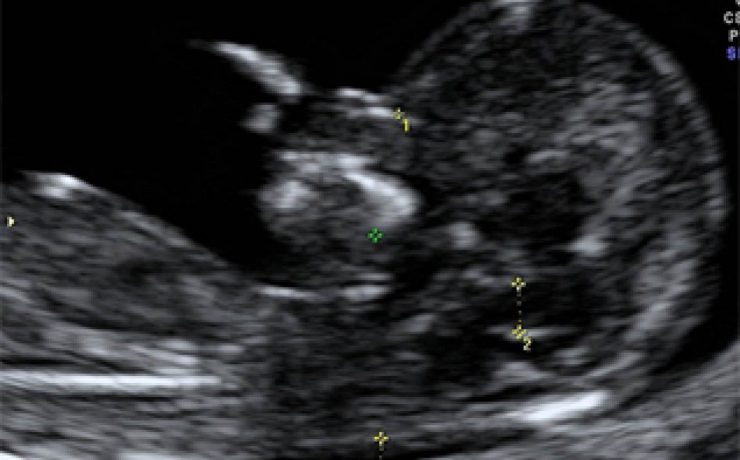

VESÍCULA DE PORCELANA

Es un término que se ha utilizado para describir la decoloración azulosa y la consistencia quebradiza de una vesícula biliar con calcificación extensa en su pared. Es una manifestación inusual de la colecistitis crónica, su máxima incidencia es la sexta década de la vida, tiene pocos síntomas generalmente dolor intermitente